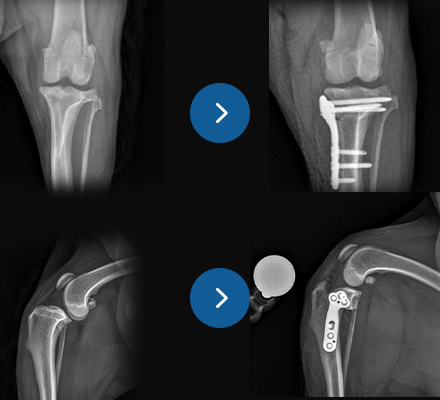

십자인대 질환

- TPLO

- 9살, 11kg, 아메리칸코커스패니엘

십자인대 질환에 대해 TPLO 수술을 진행하였습니다. 수술 직후 방사선에서 절골선이 보이지 않습니다.

정교하고 안정적인 수술로 다음날부터 산책이 가능합니다.

십자인대 질환

- 5 hole TPLO

- 11살 3kg 말티즈

다양한 회사의 플레이트 제품을 가지고 있어서 환자 맞춤으로 수술이 가능합니다.

일반적으로 TPLO 수술 시 6홀 플레이트를 사용하는데

이 환자의 경우 뼈가 작아 5홀 플레이트를 사용하여 교정하였습니다.

슬개골탈구 3기 + 십자인대질환

- modified TPLO with jeil TPLO 1.5 modified plate(6 holes)

- 4.3kg, 치와와

특수하게 휘어진 Jeil medical 1.5 modified TPLO plate를 사용하여

소형견 환자도 안정적으로 슬개골탈구와 십자인대를 동시에 교정할 수 있습니다.

슬개골탈구 3기 + 십자인대질환

- modified TPLO with jeil TPLO 1.5 modified plate (6 holes)

- 4살 3.5kg, 말티푸

슬개골탈구 3기와 십자인대질환에 대해 modified TPLO 진행하였습니다.

Modified TPLO 전용 특수하게 휘어진 플레이트를 사용하였습니다.

환자의 무릎의 병발 질환이 있을 경우

수술 방법을 일반적인 경우와 다르게 하는 등, 환자 맞춤 수술이 중요합니다.

골절수술

- 요척골 단순골절

- 4살, 이탈리안그레이하운드

고난이도 상완골 원위부 골절

- IOHC, 상완골과골절

- 4개월 시추 2.6kg

고난이도 소형견 골절 수술